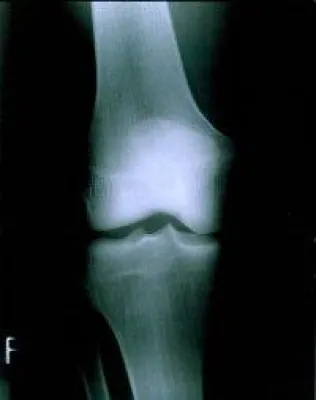

(openPR) Das Kuratorium Knochengesundheit e.V. feiert in diesem Jahr sein 25-jähriges Jubiläum und ist somit die älteste gemeinnützige bundesdeutsche Organisation, die sich mit der Knochengesundheit thematisch auseinandersetzt und sich um Patienten mit einer Osteoporose kümmert. Seit 25 Jahren sind wir Anlaufstelle für Betroffene und Interessierte und kümmern uns unter dem Motto „Ein Herz für Patienten“ darum, aktuelle wissenschaftliche und medizinische Erkenntnisse in patientengerechter Sprache in Flyern, Broschüren und der Zeitschrift MobilesLEBEN einem breiten Publikum vorzustellen.

Zur Gesunderhaltung unserer Knochen ist neben regelmäßiger körperlicher Bewegung eine ausgewogene Ernährung sehr wichtig.

Der Informationsflyer „Bone Appetit“ des Kuratorium Knochengesundheit e.V. informiert umfassend und gemäß dem aktuellen wissenschaftlichem Erkenntnisstand über die Grundlagen knochengesunder Ernährung. Es weist zudem die wichtigsten an Kalzium und Vitamin D reichen Nahrungsmittel aus und bietet einen kleinen Ernähungsfahrplan, mit dessen Hilfe man (knochen)gesunde Kost einfach in den Alltag integrieren kann.

Knochenfreundliche Ernährung hilft, der Osteoporose vorzubeugen. Von dieser Erkrankung sind nach neuesten Studien in Deutschland ein Viertel aller Menschen über 50 Jahre betroffen.